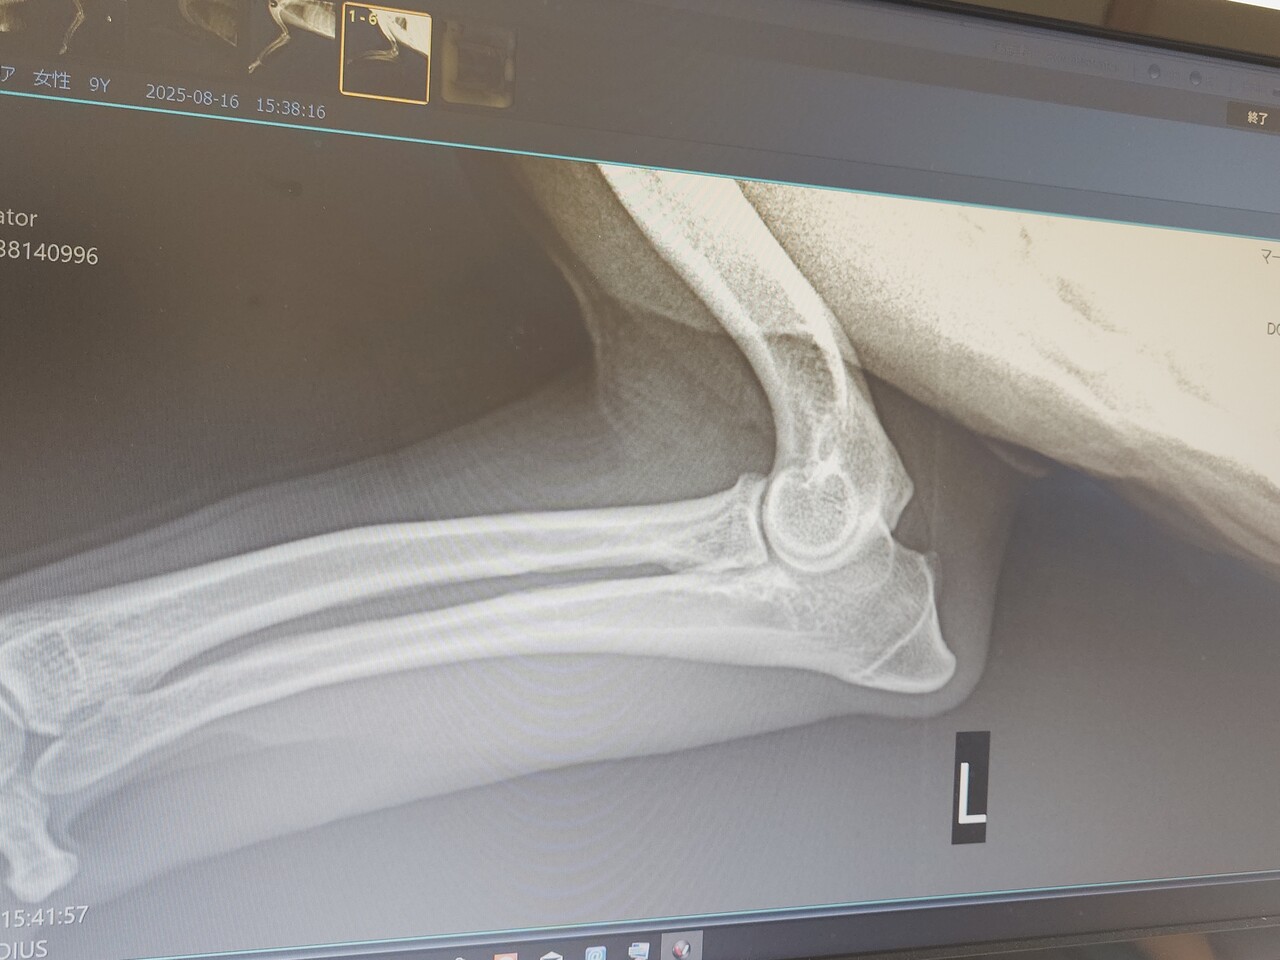

なので整形専門医のいる病院へ

レントゲンでは異常は見つからず

触診でも、いつもスーンな表情だったらしく

原因わからず。

動画を見せたところ

明らかに痛みがあり、かばっているとの事。